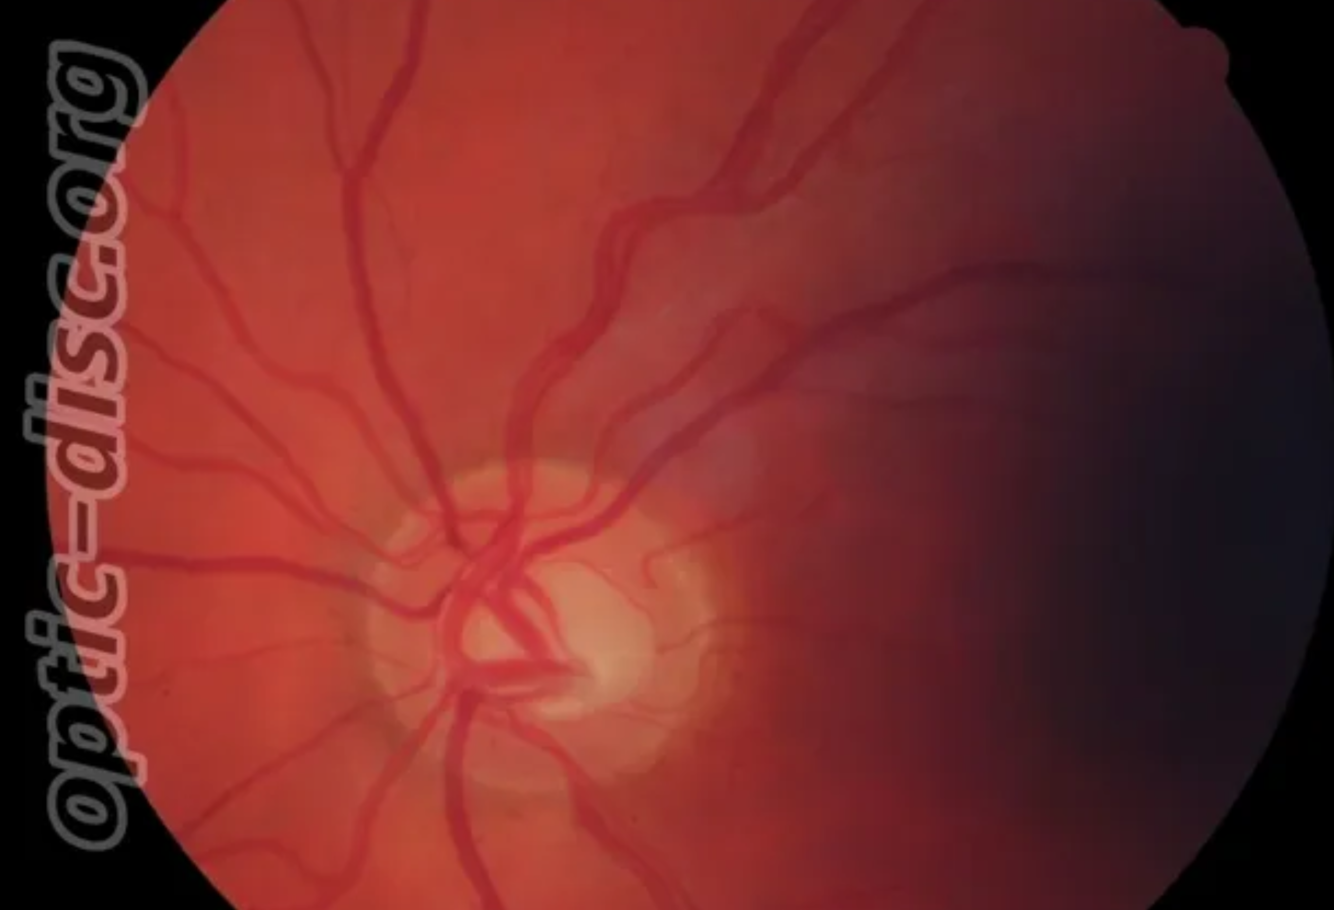

Papilloedema